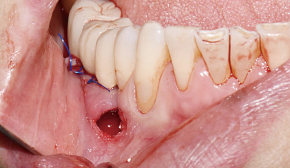

2. 터널 점막 거상

3. Bone Carrier로 골이식재 수집